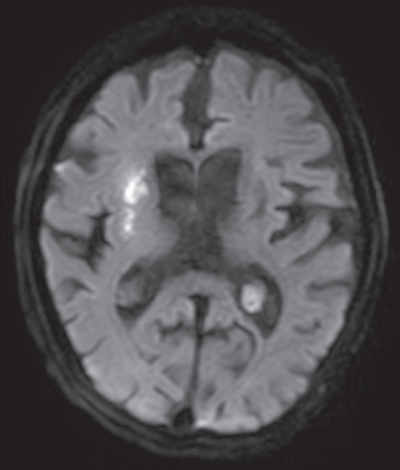

意識は清明。心拍数 82/分、整。血圧 154/82 mmHg。復唱は可能だが構音障害を認める。左顔面を含む左上下肢の不全片麻痺を認めた。来院時の頭部MRIの拡散強調像、FLAIR 像及び MRAを別に示す。